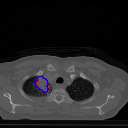

A qualitative analysis of our results reveals the strengths and weaknesses of our proposed model. In most cases, regardless of the size of the ground truth, our model predicts the tumor shapes very well. This is evident from Figure 4 where the ground truth and the prediction (by Deeply Supervised MultiResUNet) are shown in red and blue respectively. Although the tumors are in various arbitrary locations within the lung and appear in diverse sizes, the red and blue margins appear to coincide almost perfectly.

Figure 5 shows a comparison between predictions by the MultiResUNet model and Deeply supervised MultiResUNet model. It can be seen that the latter can delineate the tumor edges more accurately than the former. The ground truth (shown in red) and the prediction (shown in blue) have a more consistent alignment with each other in Deeply Supervised MultiResUNet’s prediction.